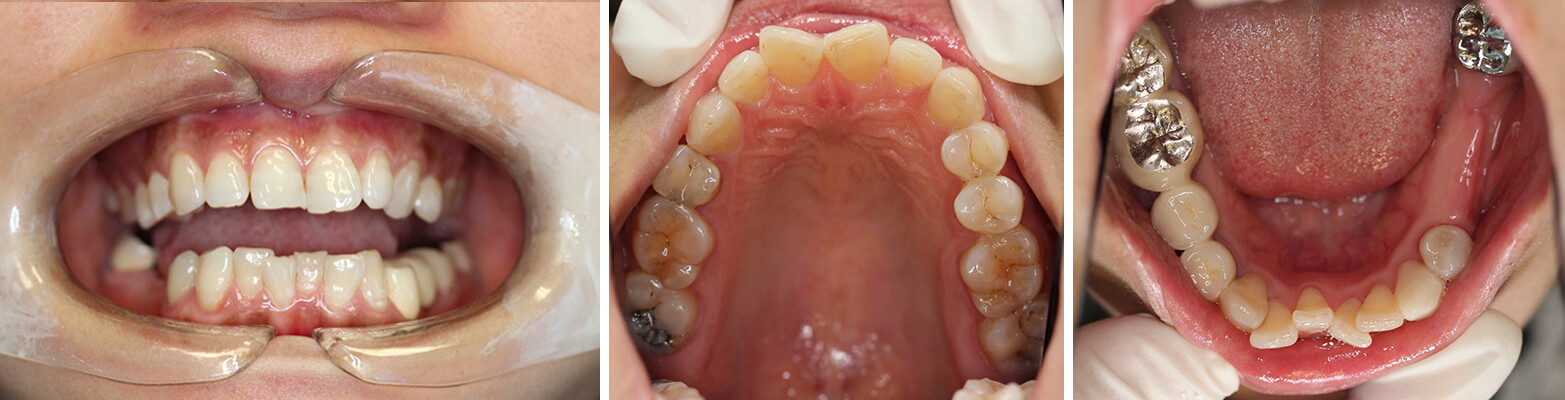

BEFORE

AFTER

Orthodontic treatment with brace, followed by 1 implant to replace lower right molar and 4 porcelain veneers to improve the aesthetics of upper anterior teeth.

Deep bite has been corrected with braces and teeth have been aligned to perfect arch and no teeth extraction required.